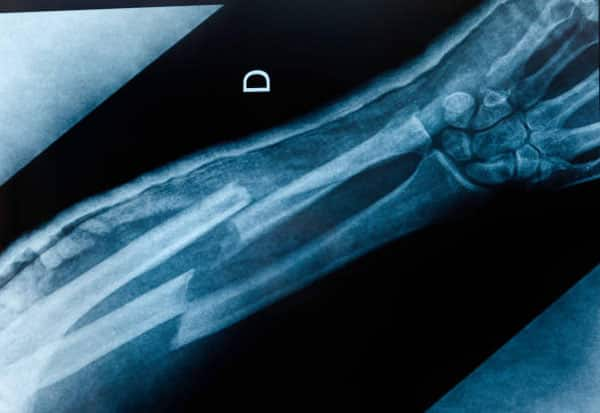

Bone fractures are among the most common injuries treated in hospitals, and their management often involves lengthy surgeries with plates, screws, or rods. While effective, these procedures require precision, time, and in many cases, a second operation to remove the implants once healing is complete.

Developed under the leadership of Dr. Lin Xianfeng, an orthopaedic surgeon from Zhejiang Province, Bone-2 has the potential to mend broken bones in as little as two to three minutes. Early experiments have shown that this adhesive can hold fractured bone fragments firmly together, reducing the time needed for complex surgical procedures.

One of the most promising aspects of Bone-2 is its biodegradability. Unlike metal plates and nails, which remain inside the body until surgically removed, Bone-2 is gradually absorbed as the bone heals. This feature could spare patients the pain and risks associated with follow-up surgeries.